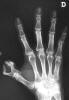

Artritis psoriásica y falange bífida.

Artritis psoriásica.

Falange distal de dedo 1º de mano, bífida.